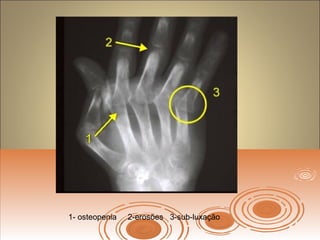

Achados radiográficosAchados radiográficos

 Osteopenia peri-articularOsteopenia peri-articular

 Diminuição do espaço articularDiminuição do espaço articular

 Presença de cisto e erosõesPresença de cisto e erosões

 Edema de partes molesEdema de partes moles

 Presença de deformidadesPresença de deformidades

1- osteopenia 2-erosões 3-sub-luxação